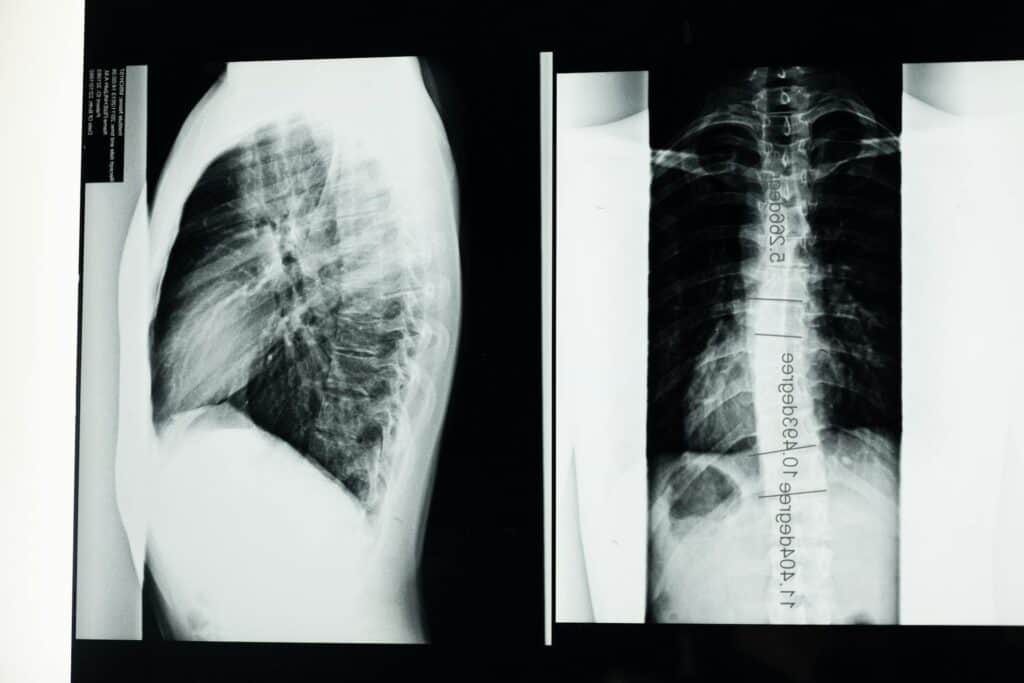

Scoliosis is a sideways curvature of the spine that measures more than 10 degrees when viewed on an X-ray. Instead of running straight down your back, the spine curves to the left or right, sometimes forming an S or C shape. In more severe cases, the spine can also rotate, causing ribs or shoulder blades to stick out more on one side.

The definitive diagnostic tool is a standing X-ray of your entire spine. This allows doctors to measure the Cobb angle, which quantifies the degree of curvature. Any curve measuring more than 10 degrees confirms a scoliosis diagnosis. The X-ray also reveals whether you have vertebral fractures, dislocations, or other structural damage from the accident.